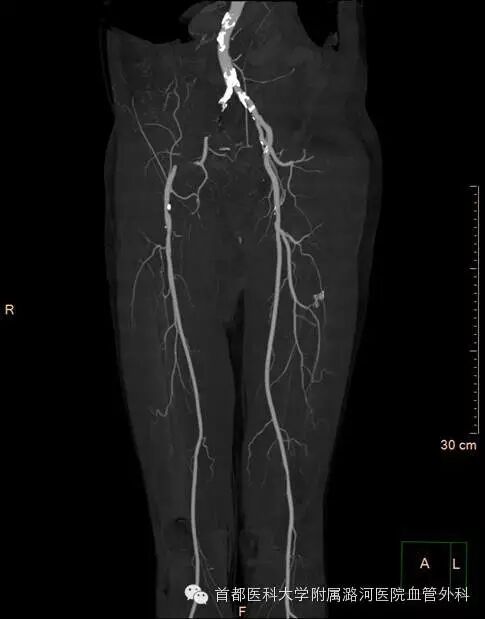

双下肢CTA:

双下肢动脉彩超:考虑右侧髂动脉起始段重度狭窄,余腔内充满低回声。